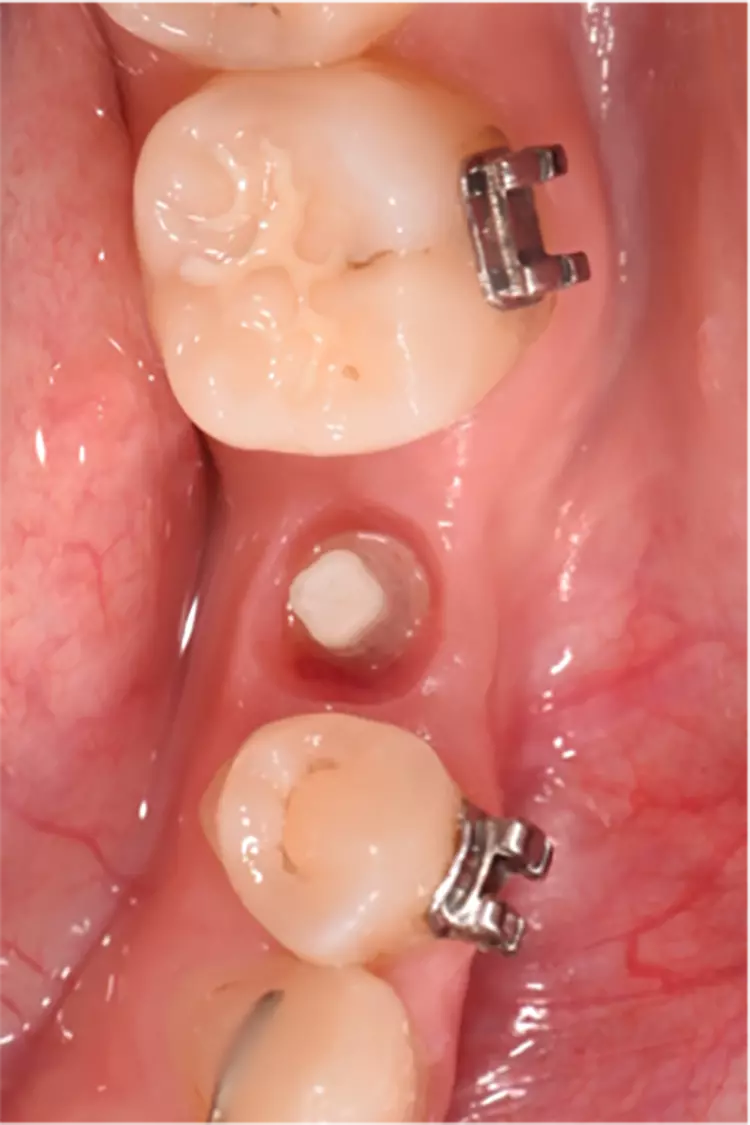

Die Implantate wurden im üblichen chirurgischen Vorgehen inseriert und sofort mit einem Provisorium aus Polymethylmethacrylat (CAD-Temp, VITA) versorgt, wobei die Provisorien außer Okklusion geschliffen wurden und darauf geachtet wurde, dass approximal nur sehr schwache Kontakte bestanden (Abb. 3a bis e). Die definitive prothetische Versorgung erfolgte im Unterkiefer nach frühestens 2 Monaten, im Oberkiefer nach frühestens 4 Monaten. Die Restaurationen wurden aus verblendetem Zirkonoxid hergestellt (VITA YZ HT / VITA VM 9, VITA).

Nach einem Jahr konnten 67 Implantate [27], nach 3 Jahren 65 Implantate [5] und nach 5 Jahren 63 Implantate [4] nachkontrolliert werden. Es gab einen Frühverlust nach 5 Wochen.

Die Überlebensrate betrug wie oben bereits erwähnt nach 5 Jahren 98,4%. Die 7,5-Jahres-Daten mit unverändert stabilen klinischen Ergebnissen sind erhoben worden und die Veröffentlichung ist in Vorbereitung.

Dies wird als Remodelling infolge des chirurgischen Eingriffs gewertet. Im weiteren Verlauf war kein zusätzlicher Knochenverlust zu beobachten. Die Ergebnisse sind besonders unter dem Aspekt zu betrachten, dass die Implantate sofort nach der Implantation mit Provisorien versorgt wurden und somit bereits unmittelbar nach dem Setzen ? wenn auch eingeschränkt ? funktionell belastet wurden. Insgesamt sind dies trotz der beiden Verluste ausgezeichnete Ergebnisse und man darf sagen, dass dieser Implantattyp hervorragend osseointegriert.